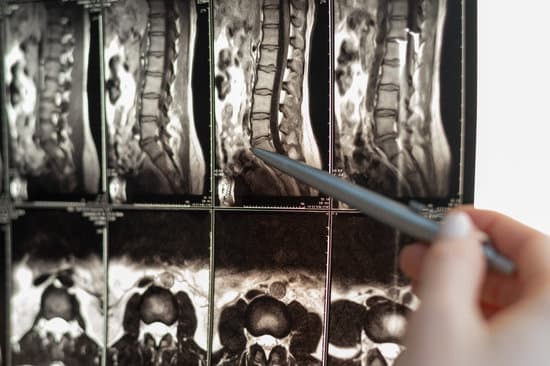

척추관 협착증의 진단

척추관 협착증을 진단하기 위해 전문의는 병력 청취 및 신체 검사를 실시하며, 필요에 따라 영상 검사를 시행합니다.

X-레이: 척추의 퇴행성 변화와 골극을 확인할 수 있습니다.

MRI(자기공명영상): 신경 압박 정도와 척추관의 상태를 정확히 확인할 수 있습니다.

CT 스캔: 척추뼈와 척추관의 구조를 세밀히 확인할 수 있습니다.